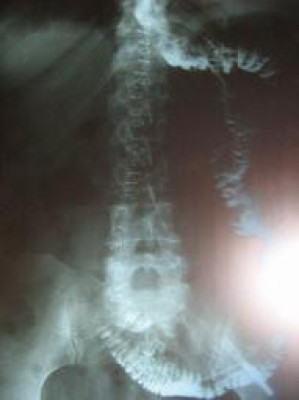

Verificación de permeabilidad de anastomosis de Y de Roux